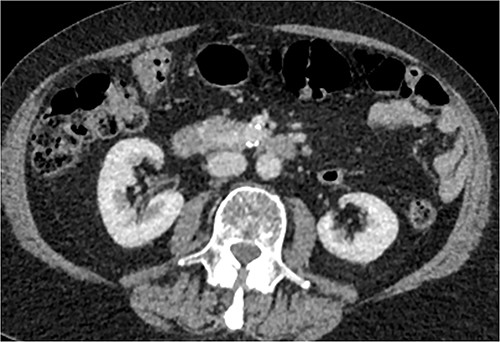

CT of abdomen and pelvis was performed, which revealed a 13 mm indeterminate lesion arising between the pancreatic uncinate process and the duodenum with coarse peripheral calcification, suspicious of primary pancreatic neoplasm or primary small bowel cancer (Figs 2–4).

Initial CT: coronal view of a 13 mm hyperattenuating region with peripheral calcification at the inferior margin of the pancreatic uncinate process and the superior margin of the duodenum.